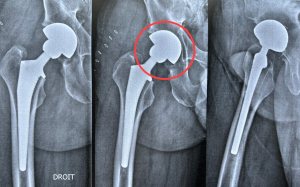

Depuis quelques semaines, ma hanche ne me fait plus mal quand je marche, et par conséquent, mon genou non plus. Fin mars, je suis allé à l’hôpital pour recevoir une prothèse. L’après-midi suivant l’opération, j’ai déjà fait mes premiers pas. Avant d’y aller, j’étais conscient que la prothèse était un cadeau de la vie bien mérité, car j’avais compris, intégré ou modifié ce qui était nécessaire. Je savais aussi que si quelque chose restait incompris, je le saurais grâce à un problème qui apparaîtrait ou une douleur qui persisterait. Et ça n’a pas loupé. En marchant, j’ai remarqué qu’il y avait du jeu dans l’articulation. La rotule sortait partiellement de son alvéole et le claquement interne que ça produisait résonnait jusque dans ma tête. C’était très inconfortable et lorsque j’essayais de me faire entendre, les mots que j’entendais systématiquement étaient « c’est normal ». Pourtant, le chirurgien n’avait jamais vu ça…🩼

Si vous comparez les deux cercles rouges, vous voyez qu’à gauche,

quand je détends ma jambe, la rotule sort de l’alvéole…